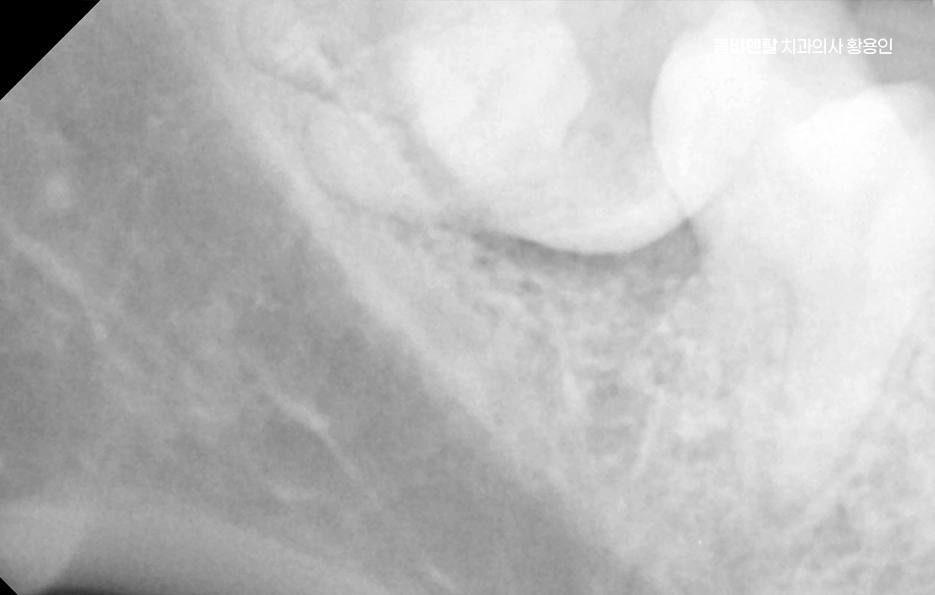

사랑니는 기본적으로 구강 내에서 가장 마지막에 나오는 치아이기 때문에 위치가 안 좋게 자라는 경우도 많고 관리가 어려운 경우도 많은데 제대로 나지 않거나, 잇몸 속에 반쯤만 머리를 내민 상태로 남아 있는 매복 사랑니는 더욱 위생관리가 어려워질 수 있었어요.

문제는 여기서 끝나지 않고 누운 사랑니와 앞 어금니 사이에 충치가 동시에 생기는 경우는 치료가 더 복잡해질 수 밖에 없는데 왜냐면 사랑니가 옆으로 누워 있으니까 앞 어금니 뒷면에 생긴 충치를 제대로 보기도 어렵고, 치료 기구가 들어갈 공간도 부족해져서 충치 치료가 더 까다로워지는 것이며 특히 앞 어금니 뒷면에 생긴 충치는 환자도 자각하기 어렵고, 진단 시기도 늦어지는 경우가 많아서 이미 신경까지 손상됐거나 신경치료가 필요한 상태로 발견되는 일도 많이 있었어요

사랑니 발치 후 충치 치료 이런 경우, 사랑니를 발치하지 않은 채로 어금니 충치 치료만 한다면 문제는 해결되지도 않고 사실상 치료적 접근도 어렵기 때문에 사랑니가 원인이 되어 어금니 충치가 생겼다면, 먼저 사랑니를 발치하고 나서 어금니를 치료하는 순서가 맞는 거예요.

또 하나 중요한 점은, 사랑니를 발치한 후 생긴 공간이 오히려 어금니 충치 치료를 더 수월하게 만들어 준다는 점으로 사랑니가 있을 때는 치료 기구 접근이 힘들었지만, 발치 후에는 시야가 확보되면서 어금니 치료가 더 깔끔하고 정확하게 가능해질 수 있어요